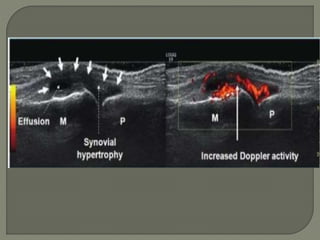

Ultrasound

1]More reliable in revealing a joint effusion in early cases.

Widening of space between capsule and bone of > 2mm

indicates effusion.

2]Echo-free - transient synovitis

3]Positively echogenic septic arthritis

Joint effusion positive USG: echo seen Positive USG : echo free

Synovial membrane

hypertrophy

Positive Positive

Colour Doppler USG increased normal

Ultrasound 1]More reliable inrevealing a joint effusion in early cases. Widening of space between capsule and bone of > 2mm indicates effusion. 2]Echo-free - transient synovitis 3]Positively echogenic septic arthritis

• 49.

Oblique sagittal ultrasoundof the hip of a 17-month-old child with septic arthritis shows an echogenic effusion and synovitis

S. Arttrities Purulent infectionof the hip joint space Transient synovities self-limiting acute inflammatory condition affecting the synovial lining of the hip. Joint effusion positive USG: echo seen Positive USG : echo free Synovial membrane hypertrophy Positive Positive Signal abnormality in adjacent bone marrow on MRI Positive Negative DWI imaging on MRI Restriction Positive No restriction Colour Doppler USG increased normal Associated with ostiomyelities and adjuscent marrow edema yes No